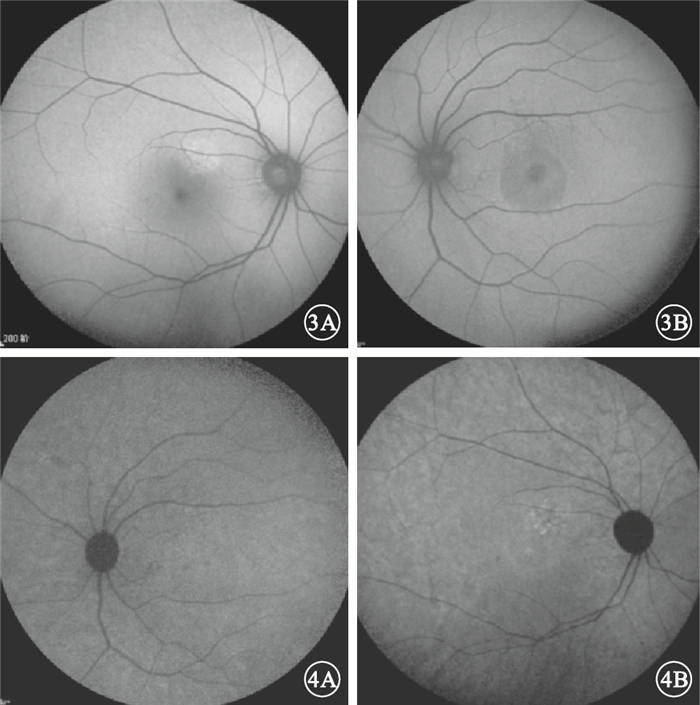

急性CSC 47只眼中,與FFA檢查可見的滲漏點對應處BLAF可表現為點狀或片狀強熒光(圖 3A)、點片狀弱熒光或斑駁熒光(圖 3B)以及無異常改變等多種表現形式。可觀察到神經上皮層脫離35只眼,占74.5%。其中,表現為圓形或橢圓形弱熒光21只眼,占60.0%,表現為強熒光14只眼,占40.0%。IRAF表現以點狀、片狀弱熒光或斑駁熒光(圖 4A)為主,強熒光(圖 4B)及無異常改變者比例相當。可觀察到神經上皮層脫離26只眼,占55.3%;均表現為圓形或橢圓形弱熒光(表 1)。

急性CSC患眼BLAF像。3A.圖 1A同眼,與FFA檢查可見的滲漏點對應處表現為片狀強熒光;3B.圖 1B同眼,與FFA檢查可見的滲漏點對應處表現為斑駁熒光??圖 4?急性CSC患眼IRAF像。圖 4A.圖 1B同眼,與FFA檢查可見的滲漏點對應處表現為點狀弱熒光;4B.圖 1A同眼,與FFA檢查可見的滲漏點對應處表現為點狀強熒光

圖3

急性CSC患眼BLAF像。3A.圖 1A同眼,與FFA檢查可見的滲漏點對應處表現為片狀強熒光;3B.圖 1B同眼,與FFA檢查可見的滲漏點對應處表現為斑駁熒光??圖 4?急性CSC患眼IRAF像。圖 4A.圖 1B同眼,與FFA檢查可見的滲漏點對應處表現為點狀弱熒光;4B.圖 1A同眼,與FFA檢查可見的滲漏點對應處表現為點狀強熒光

急性CSC 47只眼中,與FFA檢查可見的滲漏點對應處BLAF可表現為點狀或片狀強熒光(圖 3A)、點片狀弱熒光或斑駁熒光(圖 3B)以及無異常改變等多種表現形式。可觀察到神經上皮層脫離35只眼,占74.5%。其中,表現為圓形或橢圓形弱熒光21只眼,占60.0%,表現為強熒光14只眼,占40.0%。IRAF表現以點狀、片狀弱熒光或斑駁熒光(圖 4A)為主,強熒光(圖 4B)及無異常改變者比例相當。可觀察到神經上皮層脫離26只眼,占55.3%;均表現為圓形或橢圓形弱熒光(表 1)。

急性CSC患眼BLAF像。3A.圖 1A同眼,與FFA檢查可見的滲漏點對應處表現為片狀強熒光;3B.圖 1B同眼,與FFA檢查可見的滲漏點對應處表現為斑駁熒光??圖 4?急性CSC患眼IRAF像。圖 4A.圖 1B同眼,與FFA檢查可見的滲漏點對應處表現為點狀弱熒光;4B.圖 1A同眼,與FFA檢查可見的滲漏點對應處表現為點狀強熒光

圖3

急性CSC患眼BLAF像。3A.圖 1A同眼,與FFA檢查可見的滲漏點對應處表現為片狀強熒光;3B.圖 1B同眼,與FFA檢查可見的滲漏點對應處表現為斑駁熒光??圖 4?急性CSC患眼IRAF像。圖 4A.圖 1B同眼,與FFA檢查可見的滲漏點對應處表現為點狀弱熒光;4B.圖 1A同眼,與FFA檢查可見的滲漏點對應處表現為點狀強熒光